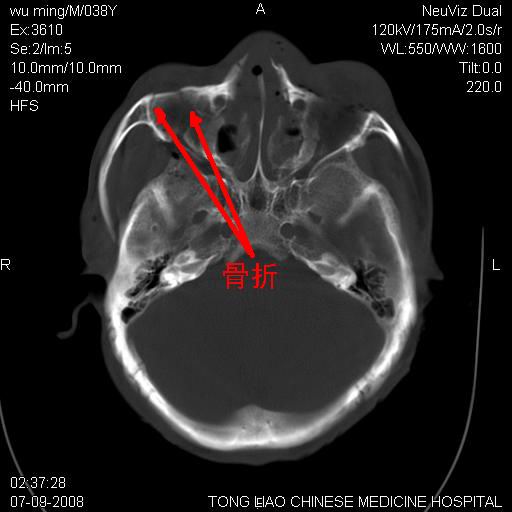

颅底多发骨折。

颅底多发骨折.上颌骨多发骨折

右侧眼眶,上颌骨,鼻骨、上颌窦等很多

骨折

1)颅底骨及颌面骨多发性骨折。2)副鼻窦及双侧鼻腔积血。

颅底、上颌骨,双侧颧骨多发骨折。死因或许与此无关,是否有腹部脏器损伤有关